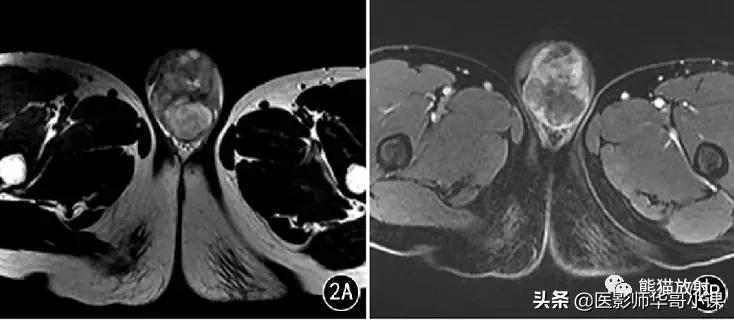

图2 男,31岁, 左侧*丸睾**混合型生殖细胞瘤 。T2WI示左侧*丸睾**混杂信号肿块;增强肿块明显不均匀强化。